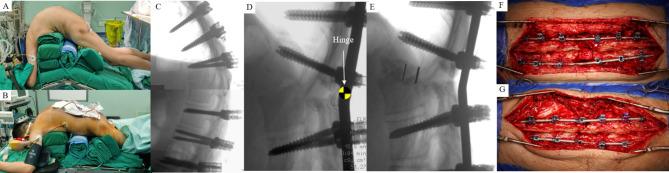

Severe kyphosis is a common condition in patients with advanced ankylosing spondylitis (AS). Although two-level osteotomy may serve as a potential alternative, it is often associated with increased blood loss and elevated surgical risks. To date, the optimal treatment for the challenging condition remains unclear. This study aims to introduce an effective strategy for the treatment of severe kyphosis secondary to AS, using one-level modified osteotomy combined with shoulders lifting correction method.

Seventy AS kyphosis who were treated with the strategy from 2012 to 2022, were reviewed retrospectively. All patients were followed up for a minimum duration of 2 years. Spinal and pelvic parameters were measured, including pelvic tilt (PT), pelvic incidence (PI), sacral slope (SS), lumber lordosis (LL), PI and LL mismatch (PI-LL), thoracic kyphosis, global kyphosis (GK), T1 pelvic angle (TPA), sagittal vertical axis (SVA), osteotomized vertebral angle (OVA), and chin-brow vertical angle (CBVA). Parameters of local osteotomized complex were measured and calculated, including the height of osteotomized complex and the length of spinal cord shortening. Clinical outcome was evaluated using Scoliosis Research Society-22 and Oswestry Disability Index scores.

Seventy patients with average age of 39.8 years were followed-up for 29.3 months. Average operation time was 373.5 min, and average blood loss was 751.0 ml. Postoperatively, sagittal balance was successfully restored. GK decreased from 90.6° to 35.6°, LL decreased from 8.0° to -35.1°, TPA decreased from 56.8° to 27.8°, and SVA decreased from 24.4 cm to 8.7 cm (P < 0.05). A harmonious and matched spinopelvic alignment was achieved. PT decreased from 37.2° to 26.3°, PI-LL decreased from 54.1° to 10.2°, and SS increased from 9.2° to 19.7°(P < 0.05). Horizontal vision was obtained with postoperative CBVA of 8.8°. Average OVA correction was up to 47.3°, and the spinal cord was shortened by 24.3 mm, with a shortening rate of 36.0%. All patients demonstrated a favorable clinical outcome. No permanent nerve damage, screw loosening, rod breakage and main vascular injury were observed. One case required revision surgery due to screw cap loosening and delayed union. Solid bone fusion was achieved in all other patients.

One-level modified osteotomy combined with shoulders lifting correction method is a safe and effective strategy for the treatment of severe AS kyphosis. This strategy offers a promising alternative for managing severe AS kyphosis, and may be particularly well-suited for individuals with concurrent osteoporosis.